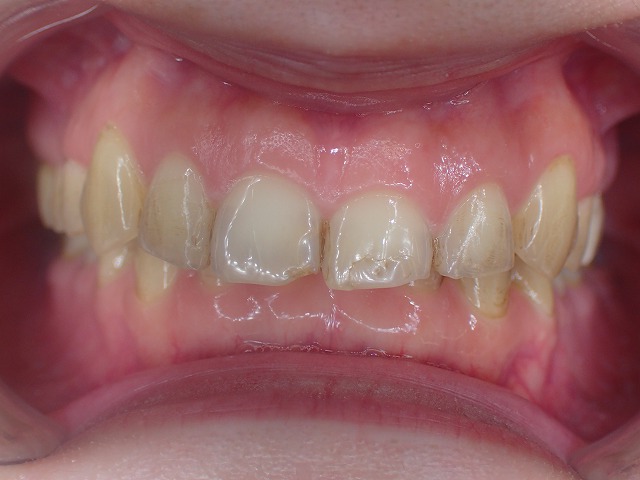

咬み合わせ診査

かなり深い過蓋咬合です。(咬み合わせが深い)

●過蓋咬合

●重度の歯ぎしり

●左右不対象

●前歯の摩耗部分にレジン充填

かなりの歯ぎしりで、前歯がバリバリに削れています。

左右不対象が気がかりです。

上顎前歯

激しく摩耗している

顎の動きで左右非対称に摩耗しているの

過蓋咬合なので上顎前歯の内側の摩耗が激しい

歯並びが左右非対称